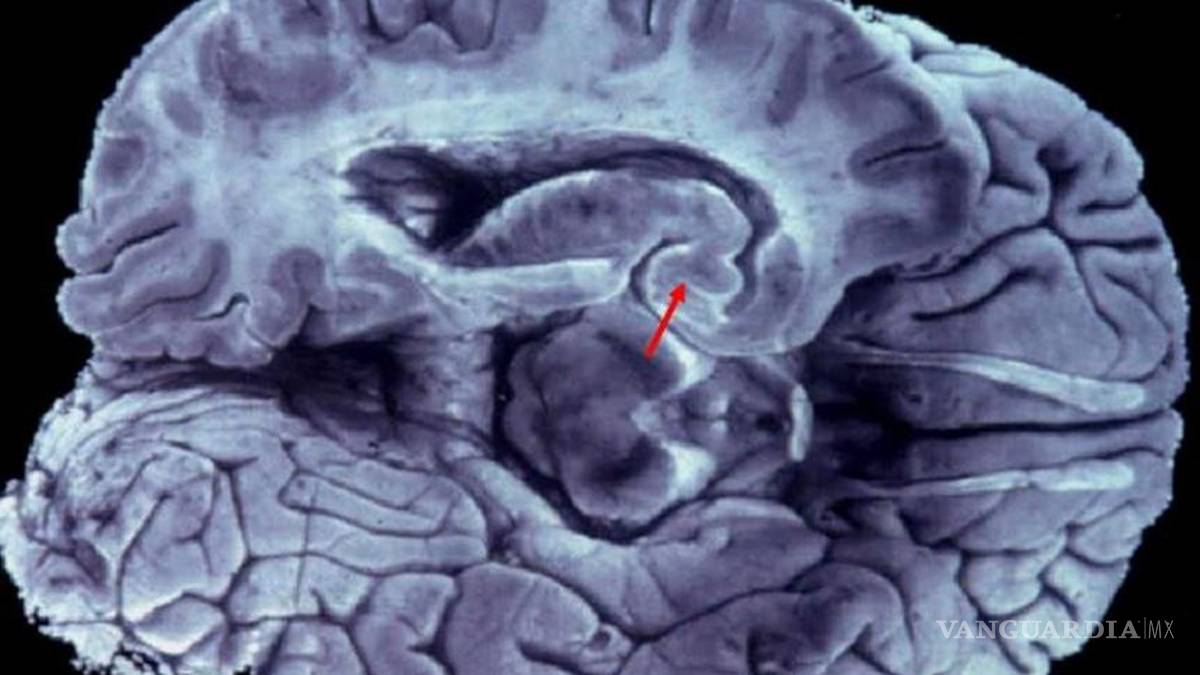

Esta enfermedad degenerativa, descrita hace más de un siglo por Alois Alzheimer, afecta entre el 3 y el 4% de la población y a partir de los 65 años.

Madrid, España.- La aparición de la enfermedad de Alzheimer es sutil. Comienza con trastornos de la memoria reciente, dificultad para encontrar palabras de uso habitual en el lenguaje, perdida de interés en las actividades diarias, olvidos frecuentes, reiteración al preguntar cosas. En ocasiones son los familiares o las personas de su entorno las primeras que aprecian estos problemas, y es muy frecuente que el paciente incluso niegue estos inicios de la enfermedad.

A pesar de los esfuerzos en investigación, a día de hoy, los complejos mecanismos por los que se desencadena la enfermedad de Alzheimer son aún una gran incógnita para la comunidad científica, por lo que seguimos sin contar con un tratamiento curativo. Sin embargo, contamos con un amplio arsenal de tratamientos que ayudan a ralentizar el proceso de degeneración neuronal que se produce durante la enfermedad. Pero para aplicarlos de forma eficaz es fundamental diagnosticar la enfermedad en su fase más temprana.

Junto con el tratamiento farmacológico para intentar enlentecer el progreso de la enfermedad, se ha demostrado que es muy recomendable la estimulación cognitiva y física de los pacientes en centros especializados. La rehabilitación cognitiva busca reforzar las funciones mentales afectadas por la enfermedad, tratando de aumentar la reserva neuronal, así como el número de conexiones entre células cerebrales y la densidad de sus redes.